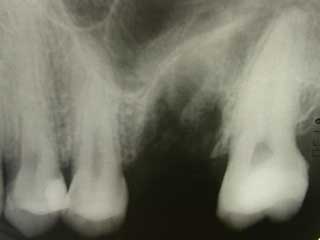

Auf dem Röntgenbild kann man vermuten, dass er extrahierte Zahn in die Kieferhöhle ragte

Die Kieferhöhle hat eine große Verbindung zur Mundhöhle über das Zahnloch

Leider können immer wieder vorhergesehene und unvorhergesehene Komplikationen auftreten. So z.B. kann bei einer Extraktion im Oberkiefer die Wurzel des Zahnes in die Kieferhöhle ragen (siehe Risiko). Wegen der Zweidimensionalität des Röntgenbildes kann man eine Eröffnung nicht sicher vorhersagen oder man müsste vorher ein DVT anfertigen. Nach der Extraktion eines verdächtigen Zahnes wird ein Nasenblastest durchgeführt. D.h. der Patient bläst in seine Nase wie beim Schnäuzen hält sich dabei die Nase luftdicht zu. Wenn nun Luft durch das Extraktionsloch blubbert, so ist die Kieferhöhle zur Mundhöhle geöffnet. Selbstverständlich muss diese dann verschlossen werden. In den nächsten Tagen darf man dann nicht Schnäuzen um die Naht nicht zu belasten. Schon bald ist nach richtiger Behandlung die Wunde ausgeheilt und die Kieferhöhle wieder dicht. Falls schon eine Kieferhöhlenentzündung besteht sollte man gleichzeitig zur Abheilung Antibiotika einnehmen. Man erzielt dadurch eine schnellere Abheilung und vermeidet dass die Kieferhöhle "chronisch" wird.